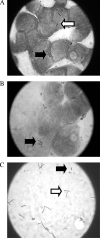

High levels of Lactobacillus, the dominant genus of the healthy human vaginal microbiota, have been epidemiologically linked to a reduced risk of infection following exposure to the sexually transmitted pathogen Neisseria gonorrhoeae. In this work, a cell culture model of gonococcal infection was adapted to examine the effects of lactobacilli on gonococcal interactions with endometrial epithelial cells in vitro. Precolonization of epithelial cells with Lactobacillus jensenii, Lactobacillus gasseri ATCC 33323, or L. gasseri ATCC 9857 reduced gonococcal adherence by nearly 50%. Lactobacilli also inhibited gonococcal invasion of epithelial cells by more than 60%, which was independent of the effect on adherence. Furthermore, lactobacilli were able to displace adherent gonococci from epithelial cells, suggesting that these organisms have potential as a postexposure prophylactic. Thus, vaginal lactobacilli have the ability to inhibit gonococci at two key steps of an infection, which might have a significant effect in determining whether the gonococcus will be able to successfully establish an infection following exposure in vivo.